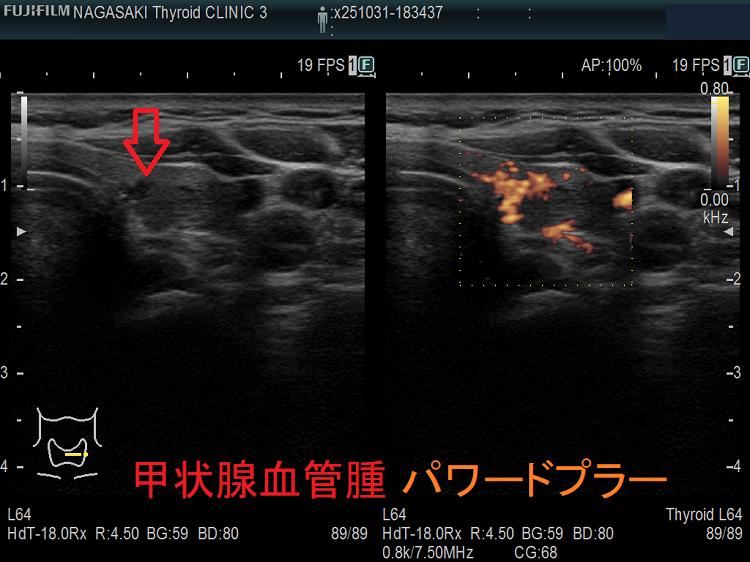

甲状腺に発生する血管腫は非常に稀で、日本の報告例もわずかです(日臨外会誌 72(3),579―583,2011)。

ケース①

ケース②

ケース③

甲状腺血管腫(拡大) ドプラーモード(eFlow);腫瘍内血管が3次元的に見え、毛玉の様。

ケース④

ケース⑤